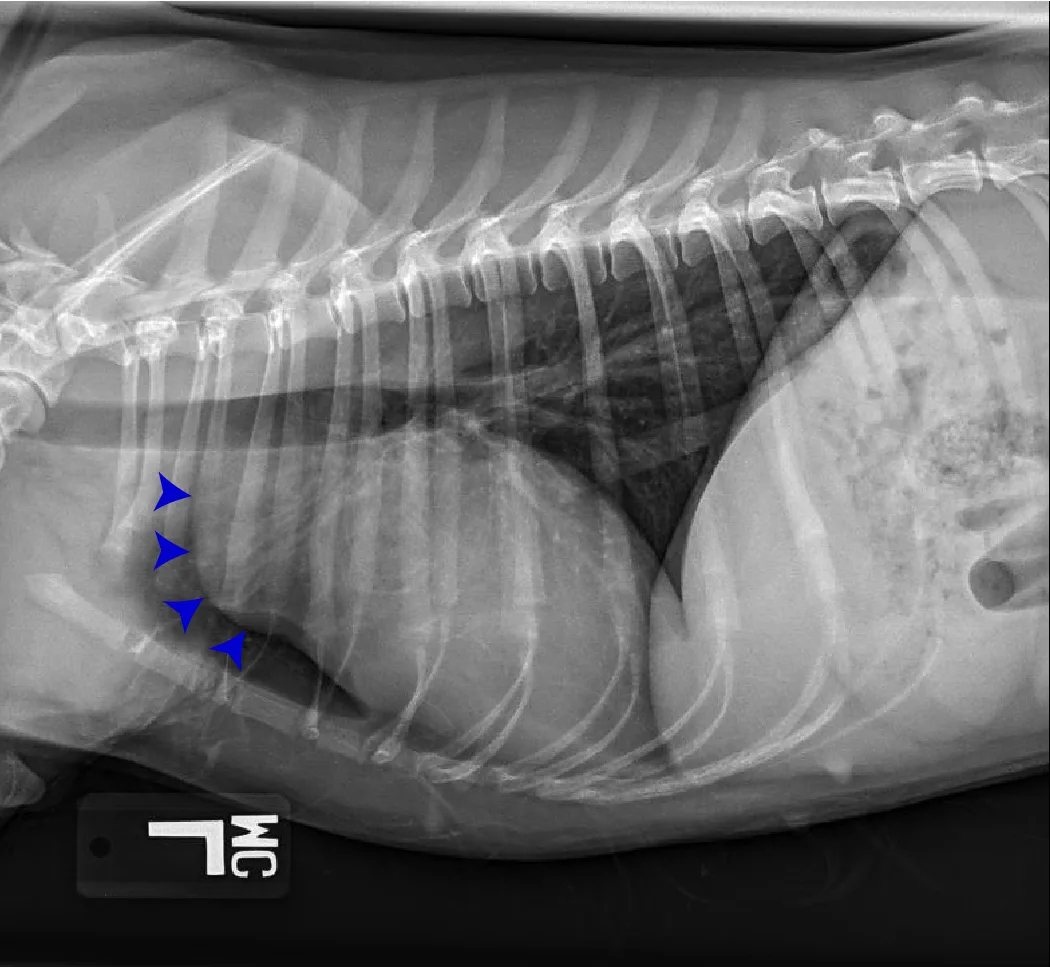

FIGURE 11 Right lateral (left) and VD (right) projections of a crossbreed dog with tricuspid valve dysplasia. The cardiac silhouette has increased width, and the regions of the right atrium and ventricle show roundness. The cardiac apex is displaced to the left secondary to right-sided enlargement (right). The caudal vena cava (arrowheads) is dilated, and there is loss of abdominal serosal detail secondary to increased systemic venous pressures and right-sided CHF, respectively. The pulmonary vasculature is small secondary to pulmonary hypoperfusion (given significant regurgitation across the tricuspid valve and decreased forward blood flow). VHS, VLAS, M-VLAS, and VRHi collected from the right lateral view are 12.3, 2.3, 2.7, and 3.8, respectively. Images courtesy of Bruna Del Nero, DACVIM (Cardiology)